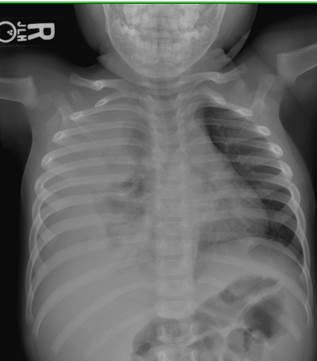

Case Study PhotoHPI: 19-month-old boy with asthma presents with fever and rapid breathing.

CXR showed pneumonia. He was started on ampicillin, IV fluids and admitted to the floor.

Comfortable and in no distress. Skin warm and dry, no rash. Posterior pharynx clear, mucous membranes moist. No tonsillar hypertrophy. Neck supple, no lymphadenopathy. Crackles and diminished breath sounds on R, normal breath sounds on left side. No wheeze, no stridor. Soft, non-distended abdomen, non-tender, no hepatosplenomegaly, no masses, normoactive bowel sounds. Spine straight with no deformities visualized No clubbing, cyanosis or edema. CNs normal, moves all limbs.

CXR:

Admitting Assessment: “19 month old with six days fever and three days respiratory symptoms—wheeze, grunting, shortness of breath, no cough. Symptoms initially responsive to albuterol, but now with little response. Most likely diagnosis is community-acquired pneumonia. Differential also includes aspiration pneumonia and foreign body aspiration. Patient currently appears well when afebrile, worse appearing when temperature rises. No supplemental O2 currently.”